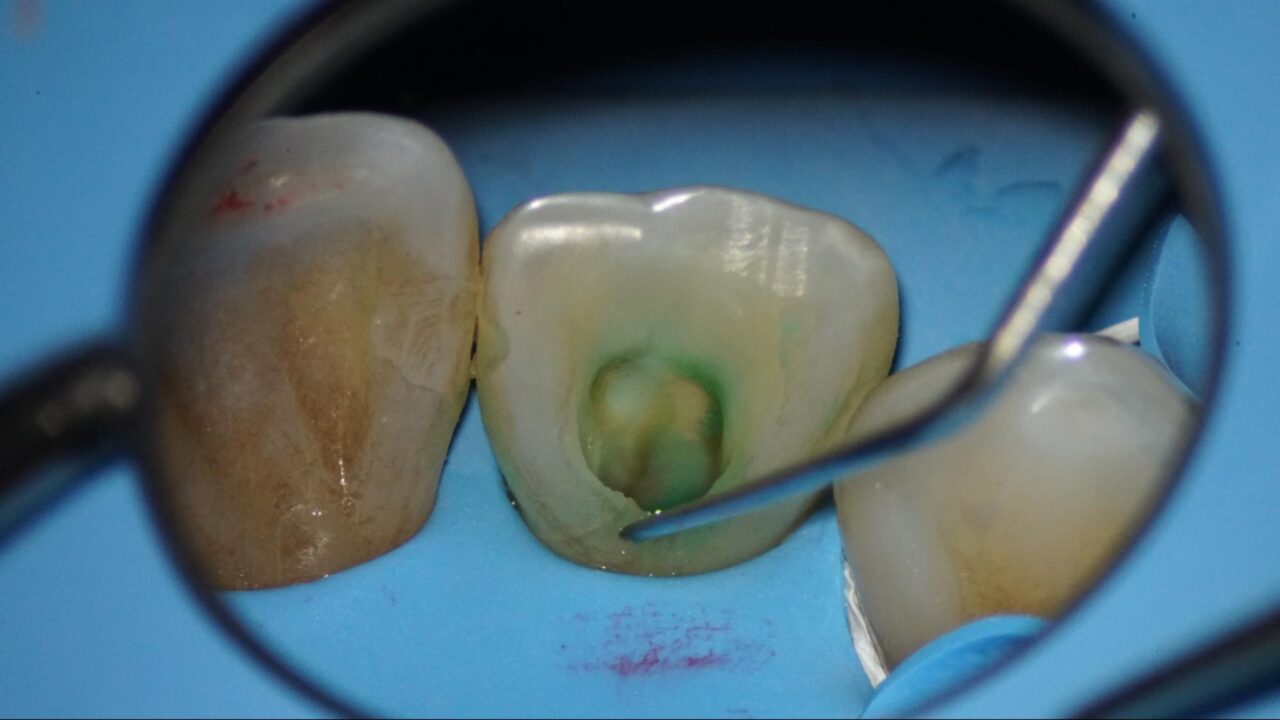

麻酔をした後にラバーダム防湿を行い、随腔内(神経がある空間)を探索すると健全な歯髄(歯の神経)は診られず、腐敗した組織が確認できます。

根管の先、根尖を確認するためにファイルを入れた状態でレントゲンを撮り、根管の長さや根尖孔の太さや状態を確認しています。